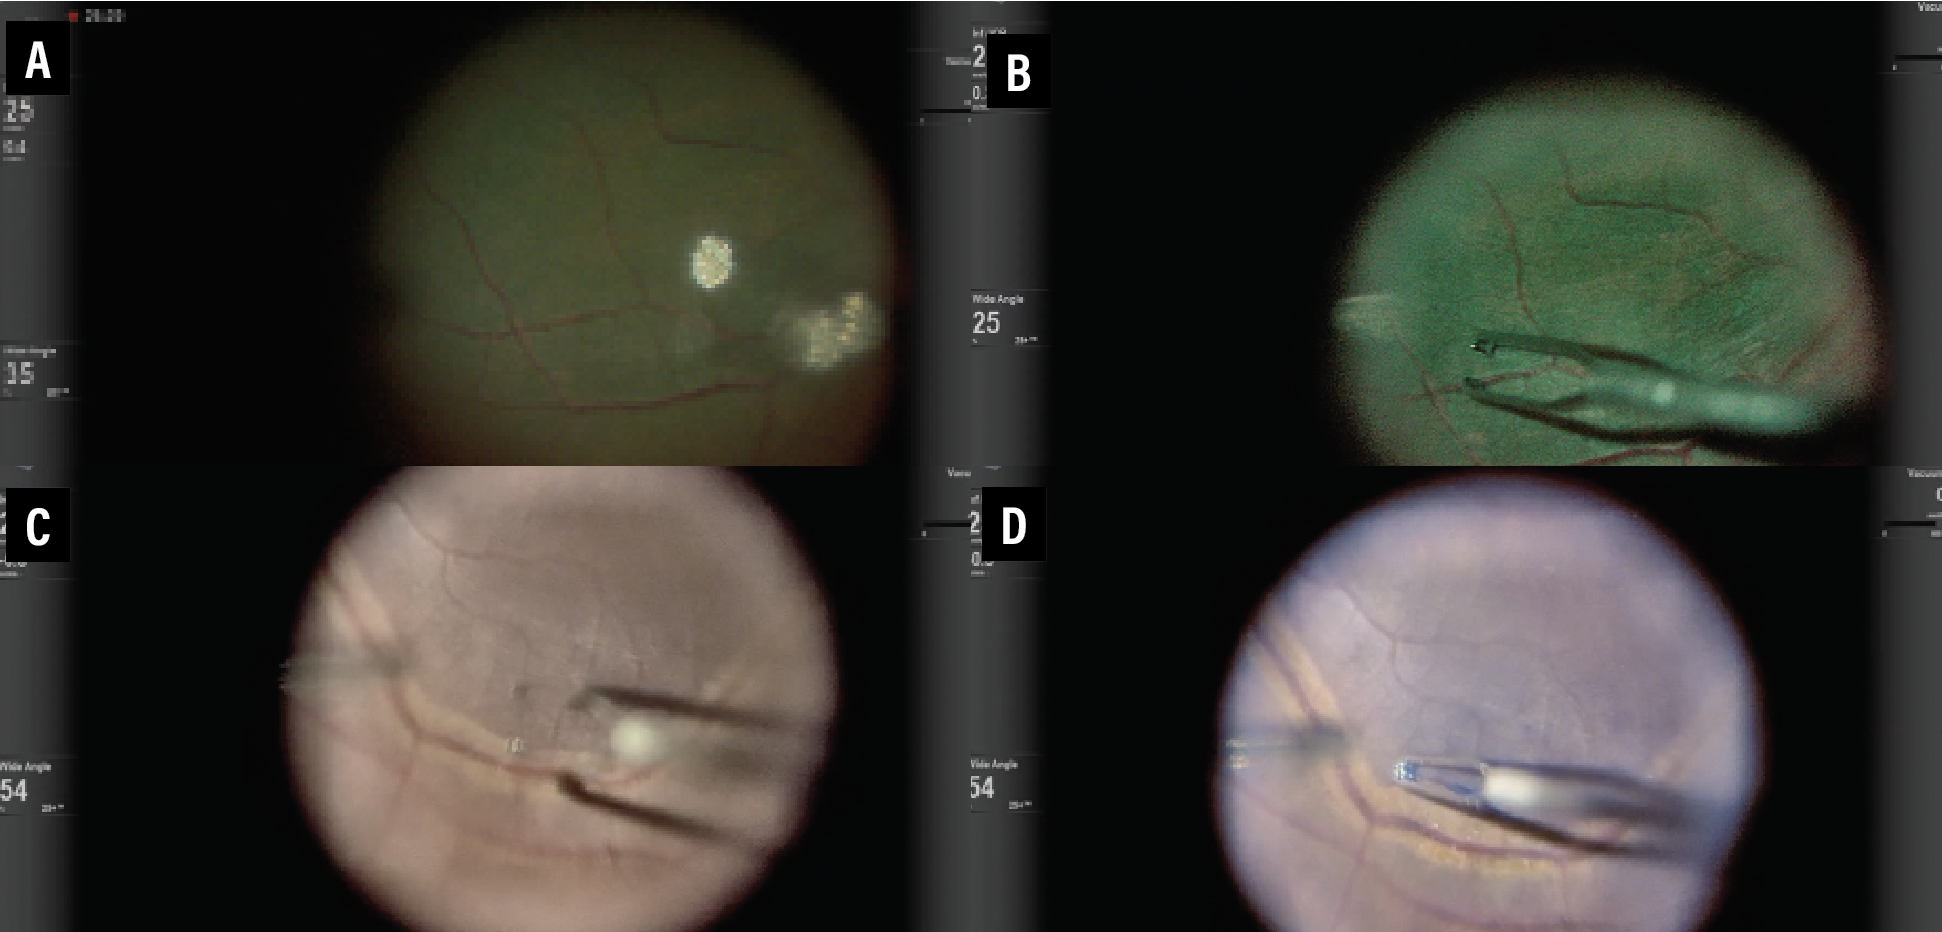

One of the main advantages of 3D HUD display includes enhanced high-resolution visualization and video chromatography. Various color profiles and camera gain adjustments can help digitally augment images to highlight pathology or areas of interest. This is especially useful to enhance visualization of vital dyes such as indocyanine green or Brilliant Blue G (Figure 1). The green boost and blue boost allow improved visualization of the internal limiting membrane after staining with ICG and BBG, respectively. Various color, contrast and tissue detail modes enable better visualization of the vitreous (Figure 2). Operators can customize the colored channels.

| Figure 1. Comparison of standard (A and C), green boost (B) and blue boost (D) views during internal limiting membrane peeling for macular hole surgery. |